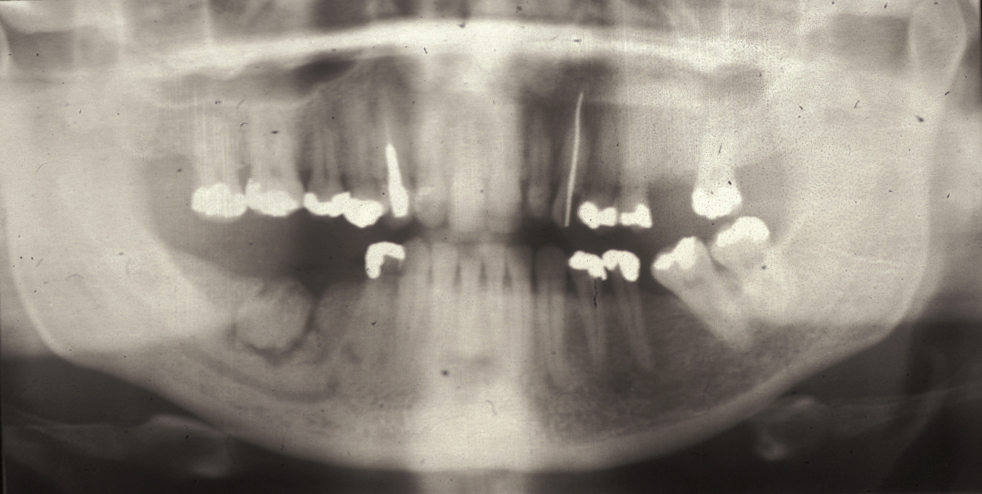

Unicystic ameloblastoma is a cystic swelling distinguished by resorbing adjacent tooth roots: histologically the lesion is an ameloblastoma but it has predominantly fluid contents. Figure 4 shows an example.

Figure 6: Unicystic amelobastoma resorbing tooth roots.

Follicular/plexiform ameloblastoma is a solid tumour, again found in the mandible. It is more aggressive in its clinical behaviour and resembles a solid tumour histologically (see Figure 5).

Figure 7: Sectional dental panoramic tomogram of the ‘soap bubble’ appearance of the solid variety of ameloblastoma.